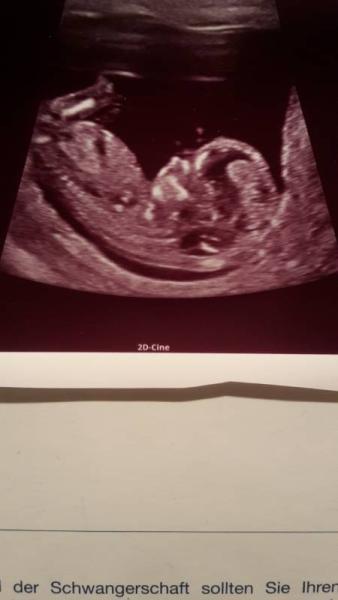

Gestern war ich beim Ultraschall. Es scheint alles in Ordnung zu sein und wahrscheinlich bekommen wir einen Jungen.

Nur vom letzten Mal. Das war 11+6